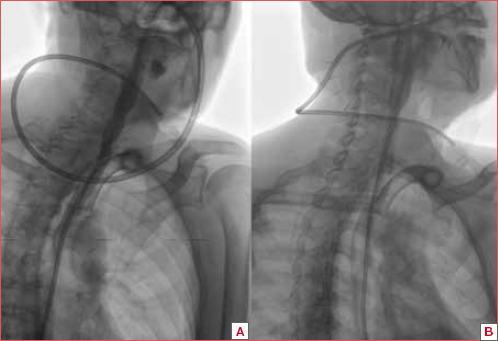

Statistically significant differences in SOAL scores were observed when comparing the three groups (ANOVA: p < 0.0001); specifically, significant differences were observed between Group 1 (average 0.89 + 1.31; CI 95%: 0-3) and Group 2 (mean 6.78 + 4.59; 95% CI: 1-24) (BH: p < 0.01), as well as between Group 1 and Group 3 (mean 11 + 7.47; 95% CI: 0-38) (BH: p < 0.01). Statistically significant differences in the SOAL scores were also identified between groups 2 and 3 (BH: p < 0.01). Figure 1 illustrates the SOAL score comparison between the three groups.

In summary, patients affected by dysphagia following RT had the worst SOAL score. However, SOAL scores of patients who only underwent laryngectomy were better than those who underwent radiotherapy.

Figure 1. SOAL score comparison between the three groups.